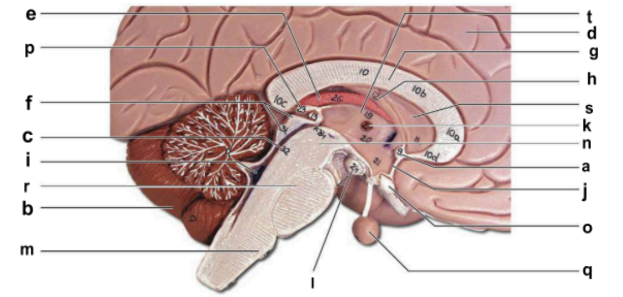

Identify the structure labeled “a” in the image.

anterior commissure

Identify the structure labeled “b” in the image.

cerebellum

Identify the structure labeled “c” in the image.

cerebral aqueduct

Identify the structure labeled “d” in the image.

cerebral hemisphere

Identify the structure labeled “e” in the image.

choroid plexus

Identify the structure labeled “f” in the image.

corpora quadrigemina

Identify the structure labeled “g” in the image.

corpos callosum

Identify the structure labeled “h” in the image.

fornix

Identify the structure labeled “i” in the image.

fourth ventricle

Identify the structure labeled “j” in the image.

hypothalamus

Identify the structure labeled “k” in the image.

interthalamic adhesion

Identify the structure labeled “l” in the image.

mammilary body

Identify the structure labeled “m” in the image.

medulla oblongata

Identify the structure labeled “n” in the image.

midbrain

Identify the structure labeled “o” in the image.

optic chiasma

Identify the structure labeled “p” in the image.

pineal gland

Identify the structure labeled “q” in the image.

pituitary gland

Identify the structure labeled “r” in the image.

pons

Identify the structure labeled “s” in the image.

septum pellucidum

Identify the structure labeled “t” in the image.

thalamus